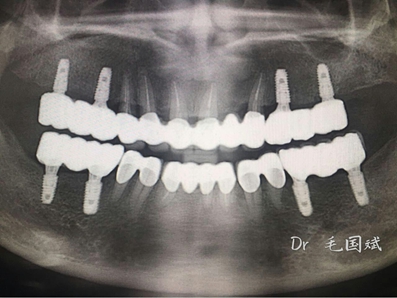

毛國斌種植病例——群討論分享